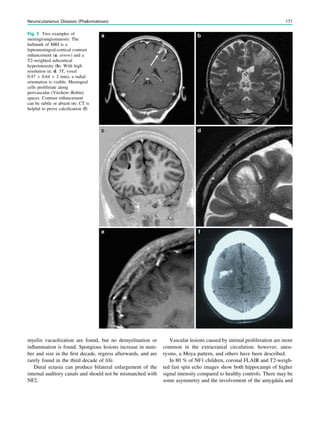

intraventricular blood; deepvein thrombosis has been reported as a rare complication. 5 Multiple Subpial Transsections 5.1 Indications Multiple subpial transsections (MST) are a disconnective procedure, introduced by Morrell and co-workers, to treat focal epilepsy in ‘‘unresectable’’ eloquent cortex (Morrell et al. 1989). The procedure is based upon experimental evidence indicating that epileptogenic discharge requires substantial side-to-side or horizontal interaction of cortical neurons and that the major functional properties of cortical tissue depend upon the vertical fiber connections of the columnar units. MST are mostly combined with resective surgery near eloquent cortex (Spencer et al. 2002). The effect on seizure outcome as a standalone procedure is measurable and may be considered as palliative surgery (Schramm et al. 2002). Some authors propose MST in children with Landau- Kleffner syndrome, but the results are variable (Cross and Neville 2009). 5.2 Surgical Technique The cortical area for MST is defined anatomically (neuro- navigation is essential) and/or electrophysiologically with intraoperative eletrocorticography. The subpial transsec- tions are performed with specially designed knives (Morrell et al. 1989). After a small pial opening, intragriseal inci- sions spaced at 5-mm intervals are placed over the crown of the cortical gyri, perpendicular to the long axis of the respective gyrus. MST (and cortical resection) are guided by repeated eletrocorticography. Morrell et al. used awake craniotomy for functional mapping in some patients. 5.3 Imaging On MRI, subpial transsections are displayed as thin strips isointense to CSF that are oriented perpendicularly to the cortical surface (Fig. 9). References Clusmann H, Kral T, Schramm J (2006) Present practice and perspective of evaluation and surgery for temporal lobe epilepsy. Zentralbl Neurochir 67(4):165–182 Clusmann H, Schramm J, Kral T et al (2002) Prognostic factors and outcome after different types of resection for temporal lobe epilepsy. J Neurosurg 97(5):1131–1141 Cross JH, Neville BG (2009) The surgical treatment of Landau– Kleffner syndrome. Epilepsia 50(Suppl 7):63–67 Cukiert A, Burattini JA, Mariani PP et al (2006) Extended, one-stage callosal section for treatment of refractory secondarily generalized epilepsy in patients with Lennox–Gastaut and Lennox-like syn- dromes. Epilepsia 47(2):371–374 Delalande O, Bulteau C, Dellatolas G et al (2007) Vertical parasagittal hemispherotomy: surgical procedures and clinical long-term out- comes in a population of 83 children. Neurosurgery 60(2 Suppl 1):ONS19–ONS32 Delalande O, Pinard JM, Basdevant C et al (1992) Hemispherotomy: a new procedure fro central disconnection. Epilepsia 33(Suppl3): 99–100 Ebeling U, Reulen HJ (1988) Neurosurgical topography of the optic radiation in the temporal lobe. Acta Neurochir (Wien) 92:29–36 Egan RA, Shults WT, So N et al (2000) Visual field deficits in conventional anterior temporal lobectomy versus amygdalohippo- campectomy. Neurology 55:1818–1822 Fig. 9 Multiple subpial transsections in a 26 year old woman with a subtotally resected FCD IIB of the left parietal lobe extending into the prescentral gyrus (c: open arrow). The subpial transsections are visualized as thin stripes in the postcentral gyrus which are isointense to CSF and oriented perpendicular to the cortical surface (a-c: arrows) Postsurgical MRI 265

• 265.

Helmstaedter C, PetzoldI, Bien CG (2011a) The cognitive conse- quence of resecting nonlesional tissues in epilepsy surgery—results from MRI- and histopathology-negative patients with temporal lobe epilepsy. Epilepsia 52(8):1402–1408 Helmstaedter C, Van Roost D, Clusmann H et al (2004) Collateral brain damage, a potential source of cognitive impairment after selective surgery for control of mesial temporal lobe epilepsy. J Neurol Neurosurg Psychiatry 75:323–326 Helmstaedter C, Richter S, Röske S et al (2008) Differential effects of temporal pole resection with amygdalohippocampectomy versus selective amygdalohippocampectomy on material-specific memory in patients with mesial temporal lobe epilepsy. Epilepsia 49(1):88–97 Helmstaedter C, Roeske S, Kaaden S et al (2011b) Hippocampal resection length and memory outcome in selective epilepsy surgery. J Neurol Neurosurg Psychiatry 82(12):1375–1381 Helmstaedter C, Van Roost D, Clusmann H et al (2004) Collateral brain damage, a potential source of cognitive impairment after selective surgery for control of mesial temporal lobe epilepsy. J Neurol Neurosurg Psychiatry 75:323–326 Hori T, Tabuchi S, Kurosaki M, et al (1993) Subtemporal amygdalo- hippocampectomy for treating medically intractable temporal lobe epilepsy. Neurosurgery 33:50–56 (discussion 56–57) Morrell F, Whisler WW, Bleck TP (1989) Multiple subpial transec- tion: a new approach to the surgical treatment of focal epilepsy. J Neurosurg 70(2):231–239 Nayel MH, Awad IA, Luders H (1991) Extent of mesiobasal resection determines outcome after temporal lobectomy for intractable complex partial seizures. Neurosurgery 29(1):55–60 Olivier A (2000) Transcortical selective amygdalohippocampectomy in temporal lobe epilepsy. Can J Neurol Sci 27(Suppl 1):S68–S76 (discussion S92–S66) Pendl G, Eder HG, Schroettner O, Leber KA (1999) Corpus callosotomy with radiosurgery. Neurosurgery 45(2):303–307 Rasmussen T (1983) Hemispherectomy for seizures revisited. Can J Neurol Sci 10(2):71–78 Renowden SA, Matkovic Z, Adams CB et al (1995) Selective amygdalohippocampectomy for hippocampal sclerosis: postopera- tive MR appearance. AJNR Am J Neuroradiol 16:1855–1861 Schramm J (2002) Hemispherectomy techniques. Neurosurg Clin North Am 37:113–134 Schramm J, Aliashkevich AF, Grunwald T (2002) Multiple subpial transections: outcome and complications in 20 patients who did not undergo resection. J Neurosurg 97(1):39–47 Schramm J, Behrens E, Entzian W (1995) Hemispherical deafferen- tiation: an alternative to functional hemipherectomy. Neurosurgery 36:509–516 Schramm J, Kral T, Clusmann H (2001) Transsylvian keyhole functional hemispherotomy. Neurosurgery 49:891–901 Schramm J, Clusmann H (2008) The surgery of epilepsy. Neurosurgery 62(Suppl 2):463–481 Schramm J, Kuczaty S, Sassen R et al (2012) Pediatric functional hemispherectomy: outcome in 92 patients. Acta Neurochir (Wien) 154(11):2017–2028 Sincoff EH, Tan Y, Abdulrauf SI (2004) White matter fiber dissection of the optic radiations of the temporal lobe and implications for surgical approaches to the temporal horn. J Neurosurg 101:739–746 Spencer DD, Spencer SS (1989) Corpus callosotomy in the treatment of medically intractable secondarily generalized seizures of children. Cleve Clin J Med 56(Suppl Pt 1):S69–S78 Spencer SS, Schramm J, Wyler A et al (2002) Multiple subpial transection for intractable partial epilepsy: an international meta- analysis. Epilepsia 43(2):141–145 Spencer DD, Spencer SS, Mattson RH et al (1984) Access to the posterior medial temporal lobe structures in the surgical treatment of temporal lobe epilepsy. Neurosurgery 15(5):667–671 Thudium MO, Campos AR, Urbach H, Clusmann H (2010) The basal temporal approach for mesial temporal surgery: sparing the Meyer loop with navigated diffusion tensor tractography. Neurosurgery 67:(2 Suppl Operative):385–390 van der Knaap LJ, van der Ham IJ (2011) How does the corpus callosum mediate interhemispheric transfer? A review. Behav Brain Res 223(1):211–221 Villemure JG, Daniel RT (2006) Peri-insular hemispherotomy in paediatric epilepsy. Childs Nerv Syst 22(8):967–981 Villemure JG, Mascott CR (1995) Peri-insular hemispherectomy: surgical principles and anatomy. Neurosurgery 36:509–516 von Lehe M, Wellmer J, Urbach H et al (2009) Insular lesionectomy for refractory epilepsy: management and outcome. Brain 132(Pt 4): 1048–1056 von Rhein B, Nelles M, Urbach H et al (2012) Neuropsychological outcome after selective amygdalohippocampectomy: subtemporal vs. transsylvian approach. J Neurol Neurosurg Psychiatry 83(9): 887–893 Yasßargil MG, Teddy PJ, Roth P (1985) Selective amygdalo-hippo- campectomy. Operative anatomy and surgical technique. Adv Tech Stand Neurosurg 12:93–123 Yeni SN, Tanriover N, Uyanik O et al (2008) Visual field defects in selective amygdalohippocampectomy for hippocampal sclerosis: the fate of Meyer’s loop during the transsylvian approach to the temporal horn. Neurosurgery 63:507–513 266 M. von Lehe and H. Urbach

• 266.

Index 0-9 10–20 system, 7 A Acutesymptomatic seizures, 207 Acute symptomatic, 25 Agenetic porencephaly, 196 Agyria, 133 Aicardi syndrome, 151, 155 Alobar, 157 Alpers–Huttenlocher syndrome, 227, 234 Ammon’s horn sclerosis, 91 Amobarbital, 54, 55 Amygdalohippocampectomy, 258 Angiocentric glioma, 109, 112, 115 Angiocentric neuroepithelial tumor (ANET), 112, 115, 186 Anterior temporal lobectomy, 258 Antineuronal antibodies, 101 Arteriovenous malformation (AVM), 185 Astrocytomas, 119, 167 Autoimmune-mediated encephalitis, 101 B Balloon cells, 138–141 Band heterotopia, 147 Bilateral convulsive seizure, 6, 25 Bilateral nodular periventricular heterotopias, 149 Bilateral perisylvian polymicrogryia, 149, 153 Bilateral periventricular, 145 Bilateral periventricular nodular heterotopia, 81 Blood oxygenation level dependent (BOLD), 44 Blood-oxygen-level dependent (BOLD) effect, 46 BPNH, 147 C CADASIL, 204, 205 Café au lait spots, 168 Callosal agenesis, 148, 151 Callosotomy, 262, 264 Capillary telangiectasias, 190, 191 Carbamazepine, 252 Cavernomas, 181–184 Celiac disease, 239–241 Cerebrofacial arteriovenous metameric syndromes, 185 CHARGE syndrome, 155 Chloral hydrate, 38 Choline-containing compounds (Cho), 58 Chorea-acanthocytosis, 248, 250, 253 Choroid plexus, 167, 168 Chronic progressive external ophtalmoplegia (CPEO), 230, 235 Classic lissencephalies, 131 CMV infections, 196 Cobblestone lissencephalies, 131 Cobblestone (type II) lissencephaly, 137 Cognard classification, 188 Complex DNT variants, 112 Complex partial, 5 Congenital arthrogyposis, 150 Congenital muscular dystrophy, 134 Corpus callosotomy, 263 Corpus callosum agnenesis, 149 Cortical dysplasia, 126, 173 Cranial vault thickening, 255 Cryptogenic epilepsies, 15 Cysticercosis, 212, 215, 217 Cytomegalovirus (CMV), 149, 208 D Dermoids, 121, 122 Developmental venous anomaly, 184, 188 Diabetes mellitus, 223, 242 Diffuse axonal brain injury, 179 Diffuse axonal injuries, 177, 180 Diffuse gliomas, 118 Double cortex syndrome, 81 Doublecortin (DCX), 133 Drug-resistant, 3 Dual pathology, 60, 68, 94 Dural arteriovenous fistulae, 188 DVAs, 188, 189 Dyke–Davidoff–Masson syndrome, 196, 223 Dyscognitive seizures, 11 Dysembryoplastic neuroepithelial tumours (DNTs), 109, 110, 113 E Echinococcosis, 215, 216 Electrical stimulation mapping, 43 Electroclinical syndromes, 15, 231 Eloquent cortex, 23 Encephaloclastic porencephaly, 196 Encephalomalacia, 195, 196 H. Urbach (ed.), MRI in Epilepsy, Medical Radiology. Diagnostic Imaging, DOI: 10.1007/978-3-642-17860-3, Ó Springer-Verlag Berlin Heidelberg 2013 267

• 267.